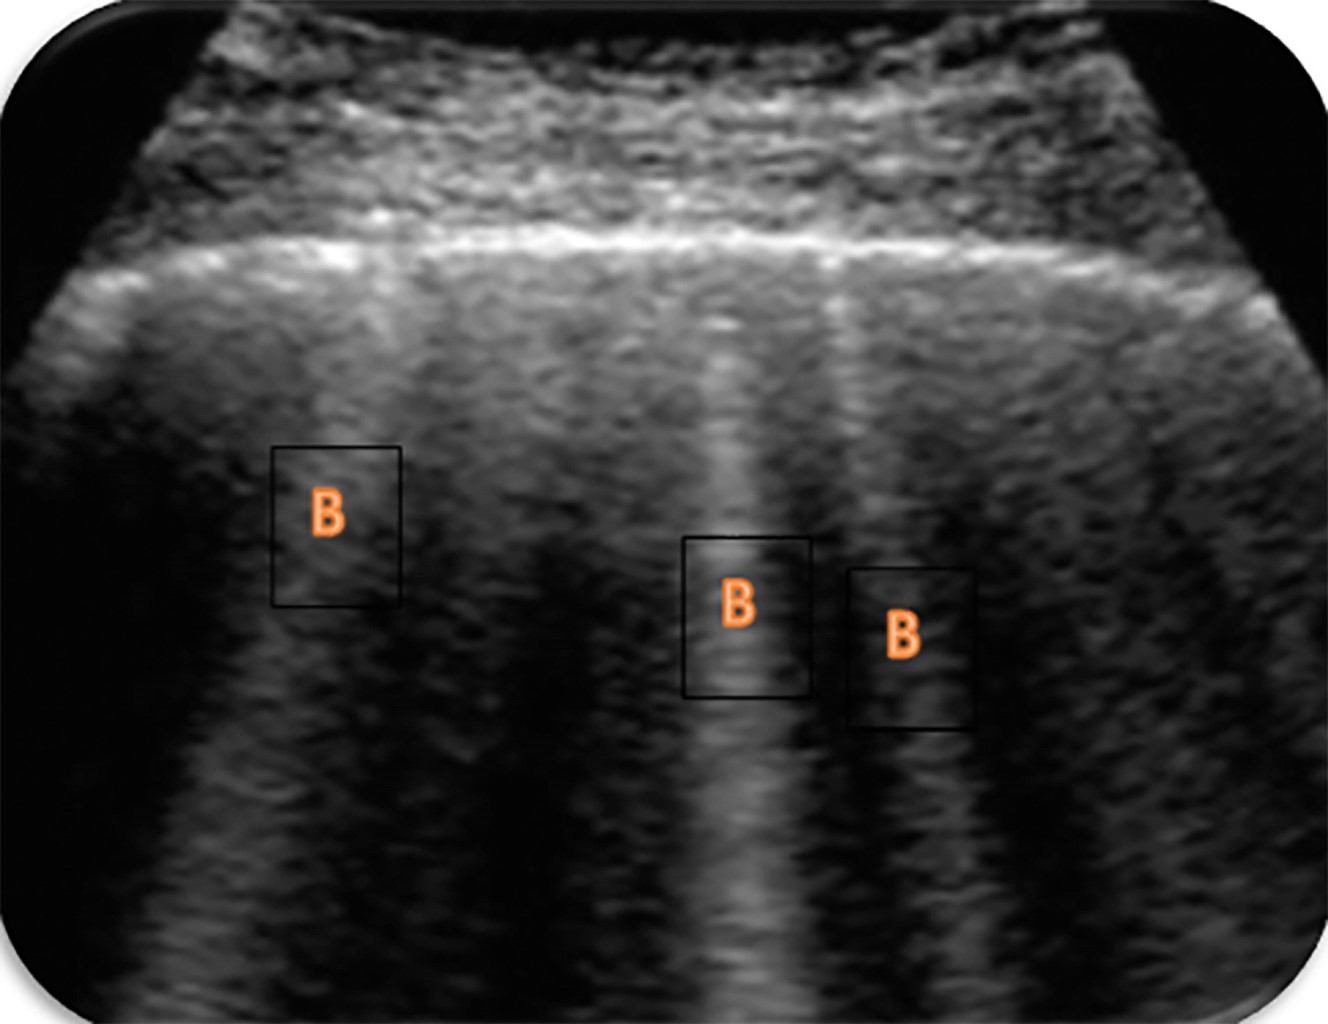

El síndrome alveolointersticial incluye varias entidades en las que se produce el engrosamiento de los septos interlobulillares con aparición de áreas en v ideo deslustrado y/o aumento del contenido del agua extravascular. Para que sean líneas B tiene que cumplir todos los siguientes criterios(9,15): líneas verticales hiperecogénicas, parten de la superficie pleural, se desplazan junto con el deslizamiento pleural, borran las líneas A, llegan al fondo de la pantalla (Figura 5).

La existencia de líneas B implica el engrosamiento de los tabiques interlobulillares, ya sea por edema, tejido conectivo, etcétera. No hay que confundir las líneas B con líneas E (enfisema), que se inician en la pared torácica o líneas Z (se inician en la pleura, pero no llegan al final de la pantalla)(16).

Desde un punto de vista anatómico los septos interlobulares están separados 7 mm, por lo que la distancia entre las líneas B nos permite deducir la localización del edema. En el edema intersticial las líneas B tendrán una separación aproximada de 7 mm (líneas B7), mientras que en el edema alveolar estarán separadas menos de 3 mm (líneas B3)(9,15).

El número de líneas B también es importante, ya que se ha demostrado que existe una correlación con la cantidad de edema. La ecografía sirve para monitorizar la evolución clínica de nuestro paciente, de tal forma que la disminución de líneas B se acompaña de una mejor situación clínica. También se ha visto cómo el número elevado de líneas B se correlaciona con una mayor presión de enclavamiento pulmonar, mayor nivel de péptido natriurético cerebral (BNP, por sus siglas en inglés) y menor fracción inspirada de oxígeno (PAFi)(16-18). En función de la distribución de las líneas B podemos hablar de(11):